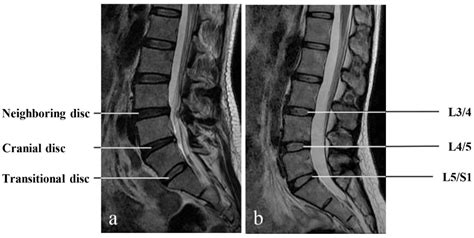

• MRI Scans: Provide information about the soft tissues and can help assess the impact of LSTV on the spinal cord and nerves.